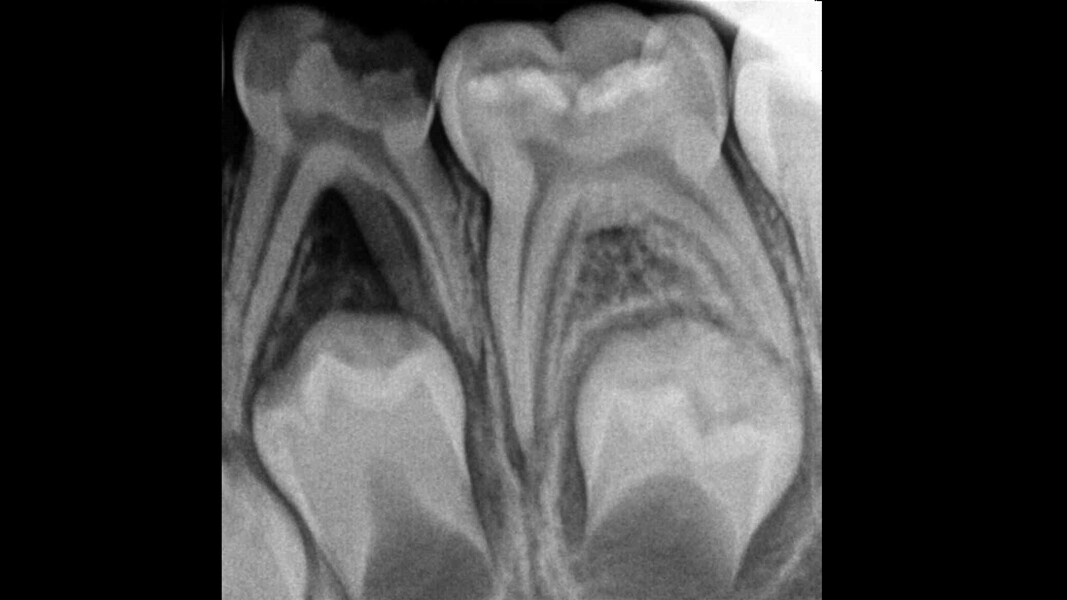

Case 1 (Figs. 1–4)

This female patient was 4 years and 7 months old and presented with pain that had lasted for several days affecting the mandibular right second primary molar. On clinical examination, a buccal gingival swelling and facial initial oedema were noted, and the tooth was found to have deep occlusal decay. Pulp necrosis and a symptomatic apical abscess were diagnosed. The patient was prescribed medication to control acute infection and rescheduled after the antibiotic treatment. At the second appointment, no pain was reported and the buccal abscess had partially receded. A decision was made to perform pulpectomy and restoration. Over-extrusion of the obturation material was observed. The 15-month re-evaluation confirmed no clinical or radiological signs of disease, and bone deposition was evident in the furcal area.